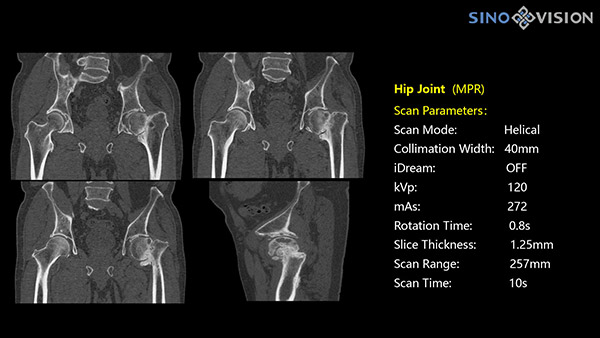

РМК

Полнофункциональный 128-резовый компьютерный томограф InsitumCT 568 - это лучшее в новом поколении широкодиапазонных томографов с 128 срезами и большой диафрагмой. Этот КТ-сканер с большой апертурой обеспечивает 128 срезов КТ с диафрагмой 76 см, улучшает разрешение изображения до 21Lp/cm, помогает точно диагностировать и лечить заболевания, а также значительно улучшает клинические характеристики и расширяемость оборудования. Позволяет реализовать визуализацию в высоком разрешении и в малых дозах лучевой нагрузки.

Полнофункциональная платформа клинической диагностики может точно определять местонахождение и диагностировать общие повреждения качественно и количественно, а также достигать полнофункциональных клинических показателей, включая обширные кардиологические исследования со сверхнизкими дозами лучевой нагрузки.